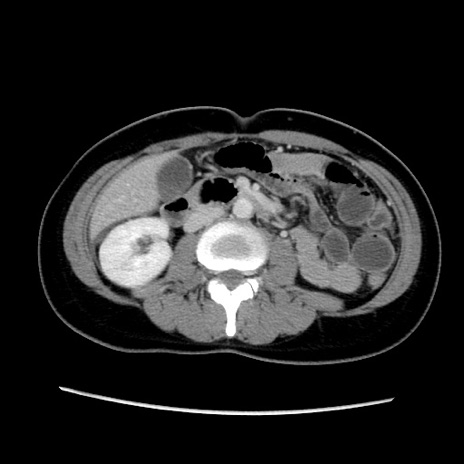

症例39(横断像)

【症例】40歳代女性

【主訴】上下腹部痛

【現病歴】2日目から下腹部痛あり。夜間は痛みで眠れなかった。昨日より上腹部痛と下痢が出現。臥位で痛みは軽快したため、休んでいた。本日になって臥位でも立位でも痛みが強くなってきたため救急要請。

【既往歴】子宮内膜症

【身体所見】部:平坦・軟、左上下腹部に圧痛あり、反跳痛あり。

【データ】WBC 21800、CRP 26.78